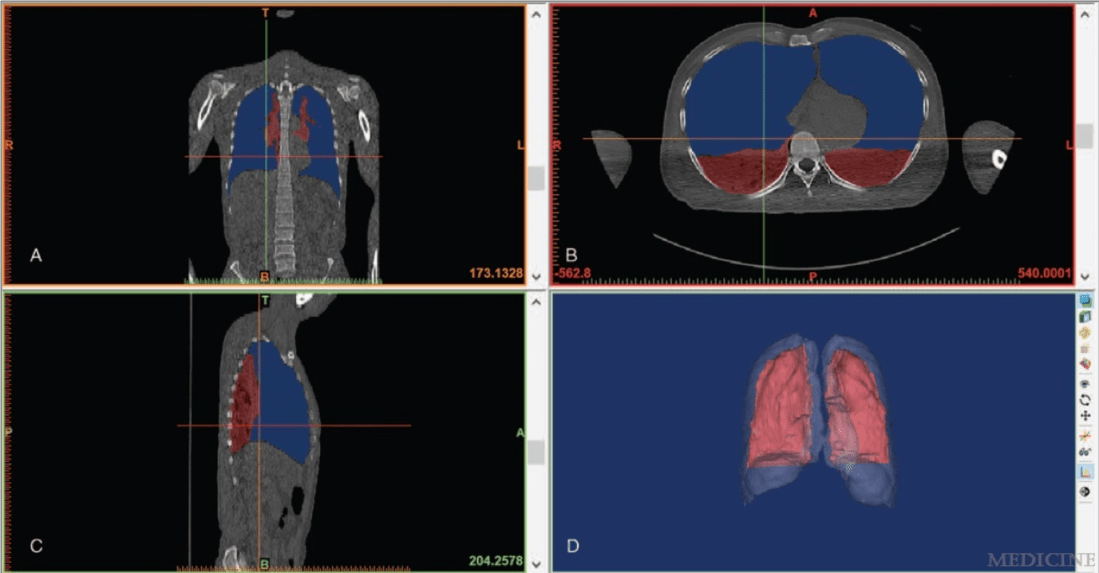

Another fatality

Inspired by Jian et al. Medicine 2018 Last Saturday (3rd November 5, 2018) I was lecturing on the BMAS Foundation Course, and during the morning coffee break I received one of my regular email alerts from PubCrawler – an Irish website that searches (or crawls) PubMed (the US National Library of Medicine) leaving you free to … Continue reading Another fatality